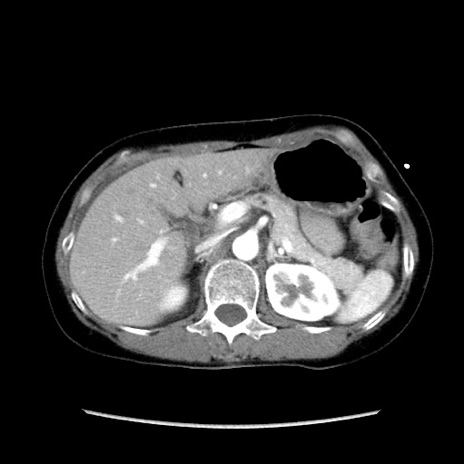

冠状断像

【症例】40歳代 女性

【主訴】上腹部痛、嘔気・嘔吐

【現病歴】約9時間前頃から急に上腹部痛、嘔気、嘔吐が出現。改善しないため救急要請。

【既往歴】子宮頚癌(広汎子宮全摘術、放射線療法)、腸閉塞

【身体所見】腹部:平坦、軟、腸雑音亢進、上腹部を中心に腹部全体に圧痛あり。

【データ】WBC 8400、CRP 0.03